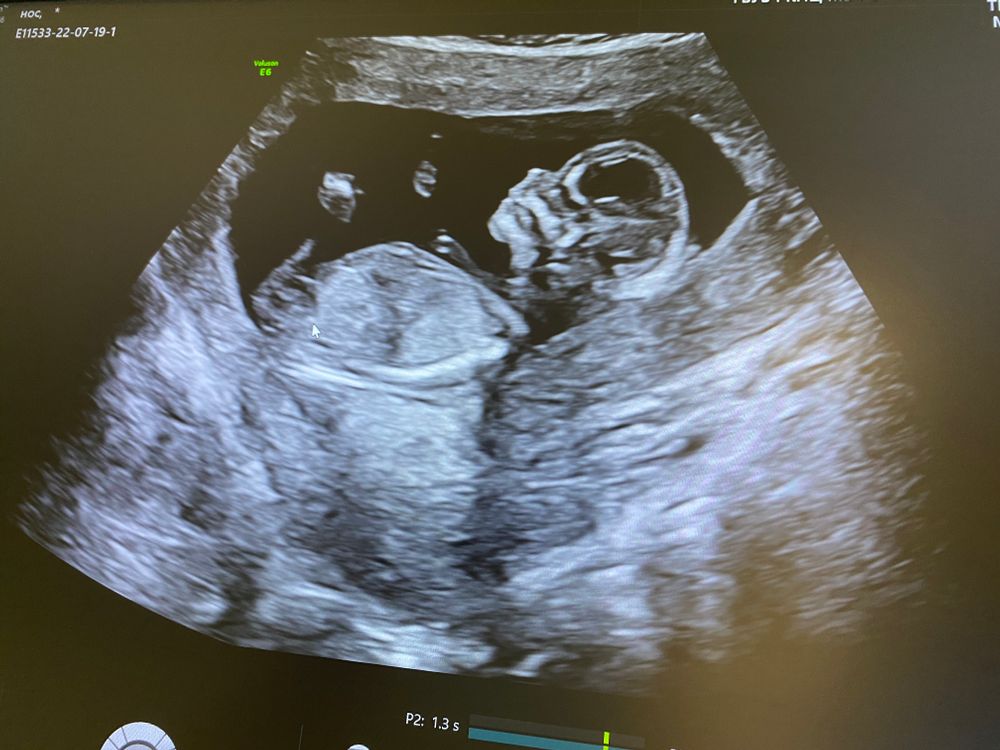

Мальчик или девочка?

Не могу понять есть ли на снимке причинное место.

Мальчик

Тут не видно)

Мальчик, я думаю

А я вот за девочку))) круглые лобики обычно у них на этих сроках)